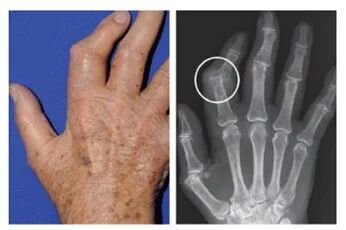

目前,惠州三院可以檢測(cè)別嘌醇過(guò)敏基因,還有專(zhuān)門(mén)為痛風(fēng)病人而設(shè)的關(guān)節(jié)彩超,以及全惠州唯一一部能探測(cè)出尿酸結(jié)晶的雙能CT,能更好地為痛風(fēng)患者的健康保駕護(hù)航!

痛風(fēng)彩超圖像

痛風(fēng)CT影像